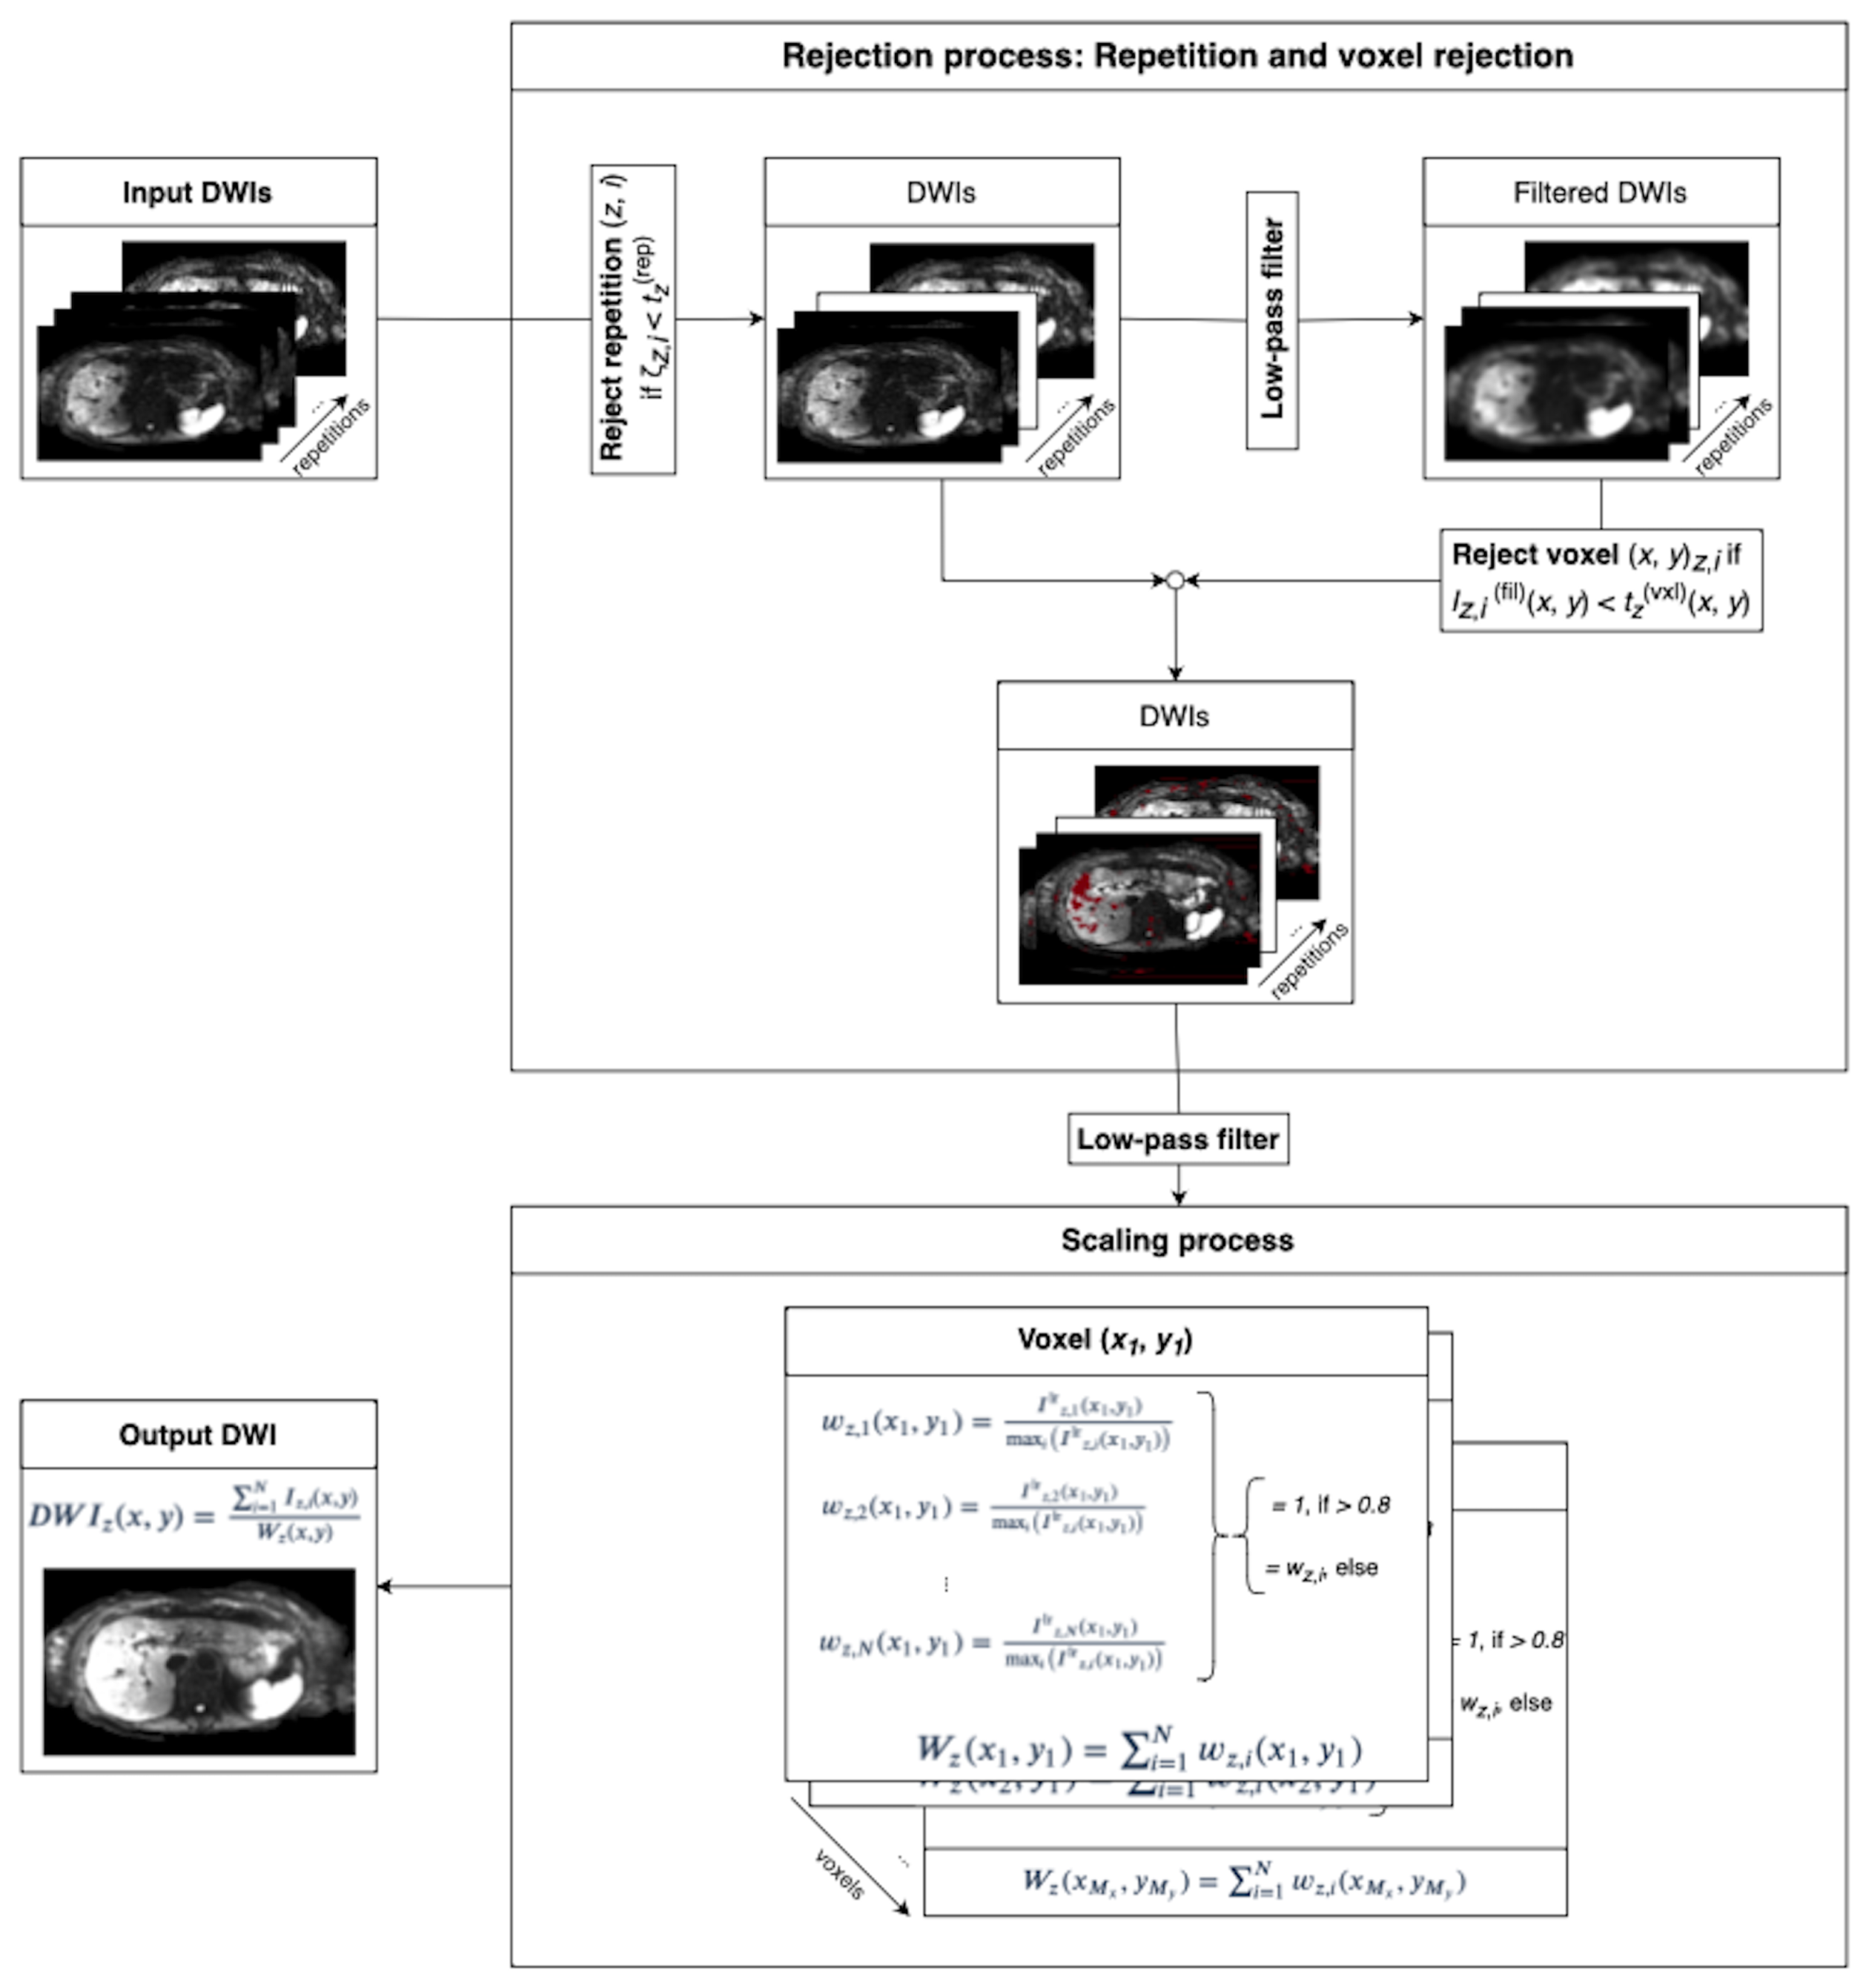

2.1. Implicit Weighted Averaging

2.2. Spatial Scaling for the Reduction of Motion-Induced Signal Loss

2.2.1. Rejection Process

2.2.2. Spatial Scaling of Average Diffusion-Weighted Images